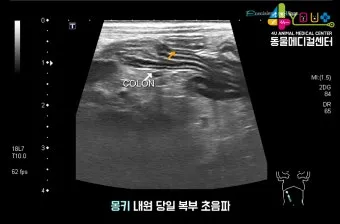

2025년 현재 강아지 복막염 치료는 과거와 비교할 수 없을 정도로 발전했어요. 조기 진단 기술의 발달과 함께 치료 성공률도 크게 향상되었거든요.